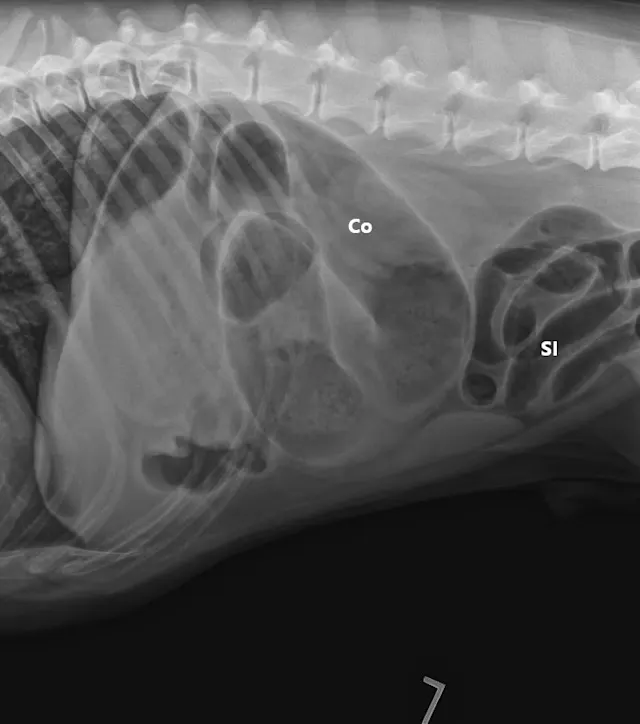

A lubricated 10 French red rubber catheter was inserted rectally and connected to a 60-mL catheter-tip syringe. Air (2 mL/kg) was injected while the anus was occluded by pinching off the anal tissue. Additional 3-view abdominal radiographs revealed normal-diameter, gas-filled small intestines; a markedly gas-distended proximal colon; soft-tissue opacity abnormally located in the right cranial abdomen; and narrowing of the distal lumen of the descending colon (Figure 2). The remainder of the radiographs were unremarkable. Radiographs were assessed by multiple board-certified radiologists, and there was a high index of suspicion for colonic torsion.

FIGURE 1A

Right lateral (A), left lateral (B), and ventrodorsal (C) abdominal radiographs demonstrating marked dilation of a single bowel loop with gas and amorphous material in the right cranial abdomen, suspected to be the colon (arrows). Caudal displacement of the small intestines (SI) can also be seen. The descending colon (Co) is poorly visualized.